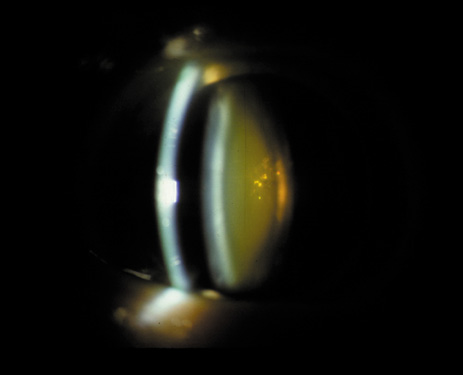

One can examine this type of cataract with direct illumination, using the narrow and broad beams of the slit-lamp to show the characteristic granular inner surface immediately in front of the posterior capsule (Fig. 13). The problem with this technique, however, is that patients may not tolerate any prolonged direct illumination because of the glare. Retroillumination is therefore more useful for revealing the outline of the opacity, since it is usually seen as an “island” in the center of the posterior capsule, which is further highlighted by the shadow cast by the opacities.33 However, in the early stages of this type of cataract, the dust-like particles that might be noticeable in the central posterior subcapsular area with direct illumination disappear or are difficult to see with retroillumination (Fig. 14). Eventually this “dusting” becomes dense enough to cast a shadow and thus appear on retroillumination. The smooth orange background of the fundus helps to highlight the rough, irregular pseudopodia-like edges of the central opacity. In advanced stages, the PSC may become a thick, calcified plaque (Fig. 15). During surgery, excessively vigorous scraping or vacuuming of the calcified opacity can lead to rupture of the posterior capsule. Usually, small remnants that are left behind after surgery are reabsorbed and do not interfere with vision; otherwise, they are easily treated with a neodymium : yttrium (Nd:YAG) aluminum garnet laser. Pathologic evidence suggests that most PSCs result from the migration of bow region cells into the potential space (along with accumulated cellular debris) between the posterior capsule and the cortex.34–36

Fig. 14. A PSC, showing vacuoles and dust-like material in the potential space between the posterior cortex and the capsule.